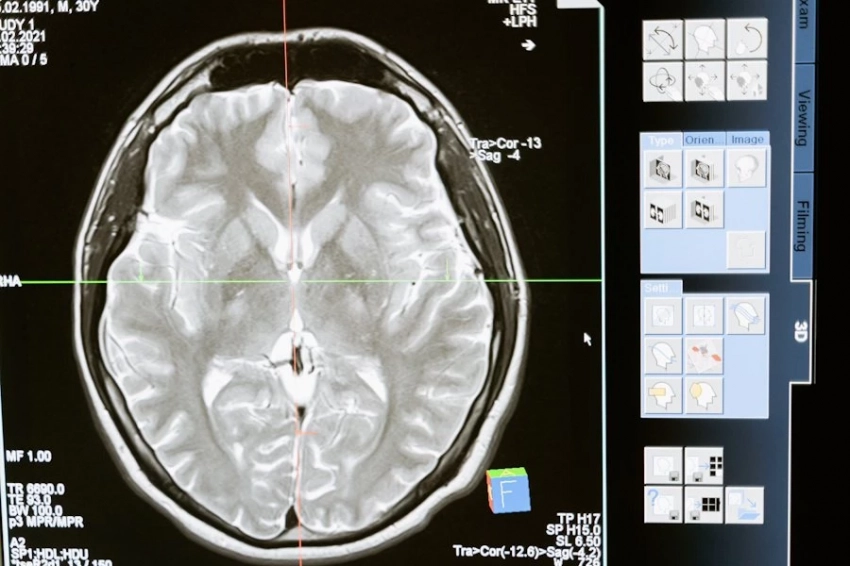

Используя данные электроэнцефалографии, ученые проанализировали нейронные паттерны добровольцев, которым предлагалось запомнить шесть событий. Оказалось, что мозг обрабатывает контекст иначе, чем детали, — за это отвечают разные области мозга, активирующиеся в разное время.